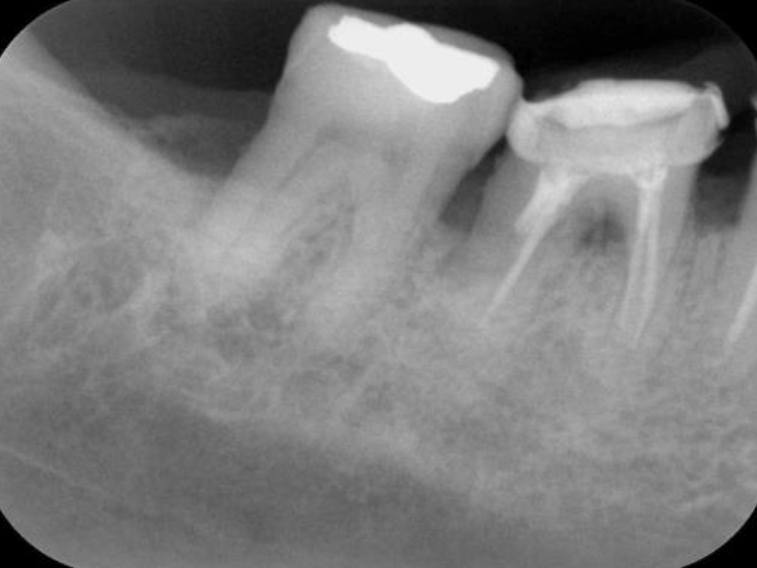

歯周基本治療・根管治療を行なった処置

処置前

根管治療・

歯周基本治療

歯周基本治療後

処置前(レントゲン)

根管治療・歯周基本治療(レントゲン)

(レントゲン)

初診時年齢:

治療:歯周病治療、う蝕治療

治療法:歯周基本治療、感染根管治療

治療期間:6ヶ月

費用:保険診療

リスク・副作用:感染根管処置中に腫れ、痛みが出ることがありますが時間とともに治ります。